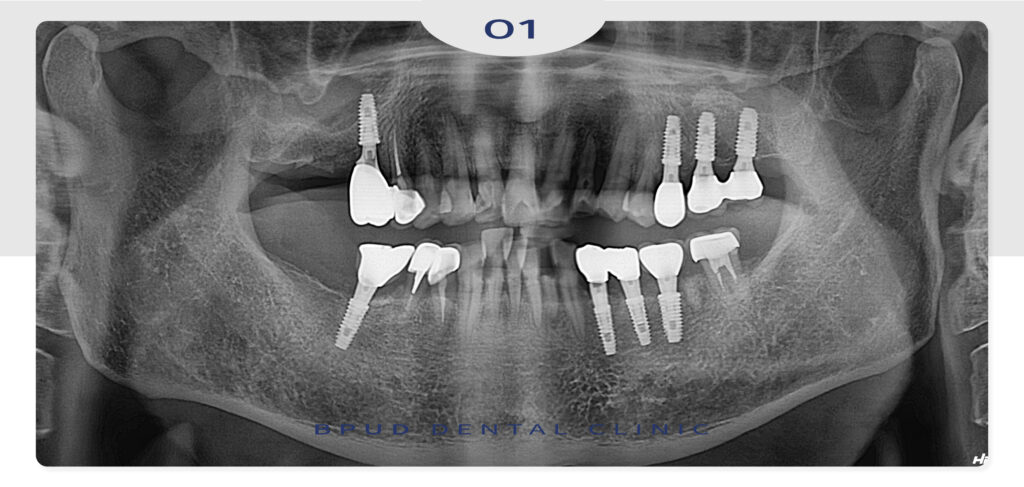

양쪽 옆의 앞니들을 먼저 신경치료 한 후,

발치 하여 미리 만들어 둔 임시치아를 사용하시는 동안

최종 보철물의 모양과 색상에 대한 충분한 상의 후

4주 정도 잇몸 치유 기간을 기다려준 뒤

인상채득 후 보철을 장착하였습니다.